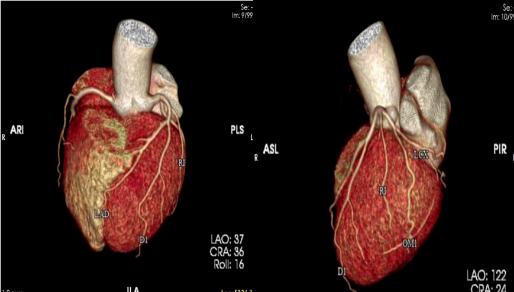

我院放射科通过 CT 联影 UCT-710

成功开展

首例冠脉动脉 CT 血管造影(CTA)检查

填补了我院在此项技术的空白

此种方法是将造影剂通过静脉途径以 4-6ml/s 的速度输入患者体内,利用人工智能、软件智能跟踪及心电门控等技术,对冠状动脉及其分支,心脏室壁运动等进行清晰显示。与传统冠脉造影相比,冠脉 CTA 对于冠脉开口变异,能更好地显示血管的开口情况,更好地确定冠脉斑块的性质, 并能显示冠脉以外的病变:如心肌桥、肿瘤等,对心脏和大血管解剖结构的显示优良。